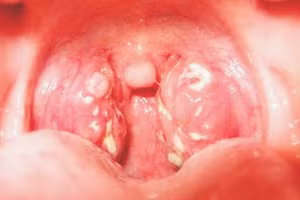

GD&TĐ - Bệnh bạch hầu là một bệnh nhiễm trùng truyền nhiễm do vi khuẩn có tên Corynebacteria diphtheriae gây ra.

GD&TĐ - Bạch hầu là một bệnh nhiễm trùng truyền nhiễm và có khả năng đe dọa tính mạng do độc tố (chất độc) được tạo ra bởi vi khuẩn.